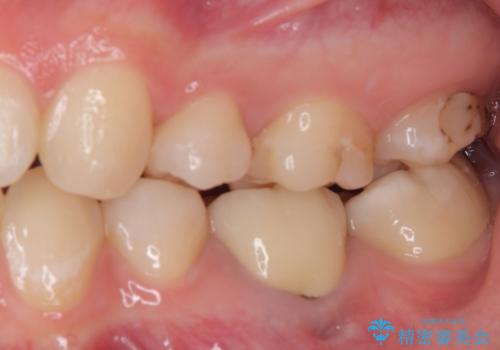

奥歯も著しく茶色に変色していたため、同様にオールセラミッククラウンにて補綴治療を行うこととしました。

明るく自然な口元になりました。